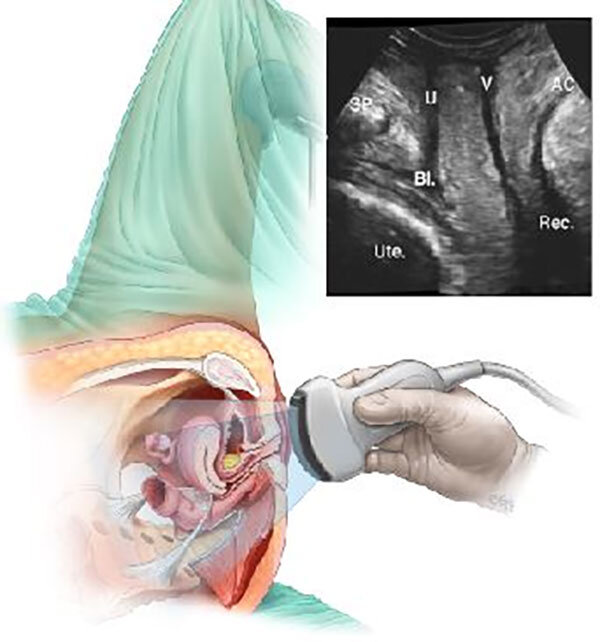

رادیولوژی